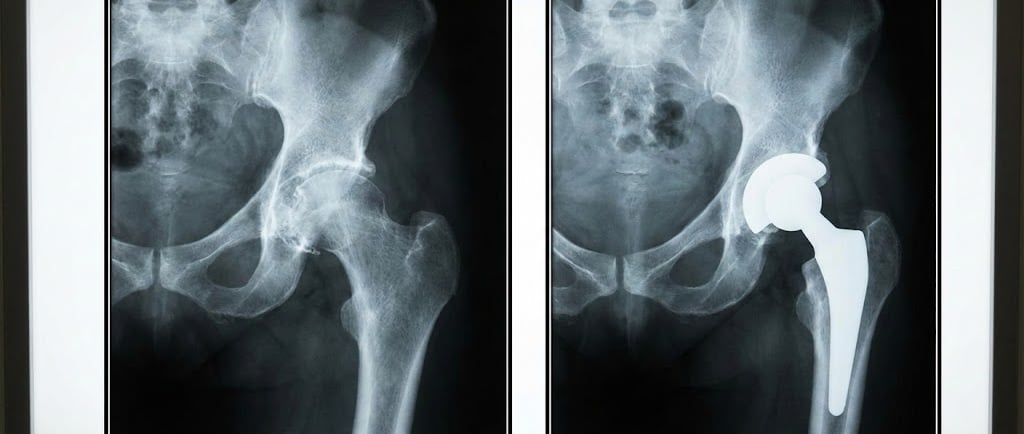

Radiografia (exame principal): mostra estreitamento do espaço articular, osteófitos e alterações ósseas. Geralmente, basta a incidência AP da pelve e perfil do quadril.

Artroplastia total de quadril (prótese): substitui a articulação danificada por implante, aliviando dor e restaurando mobilidade em casos avançados.